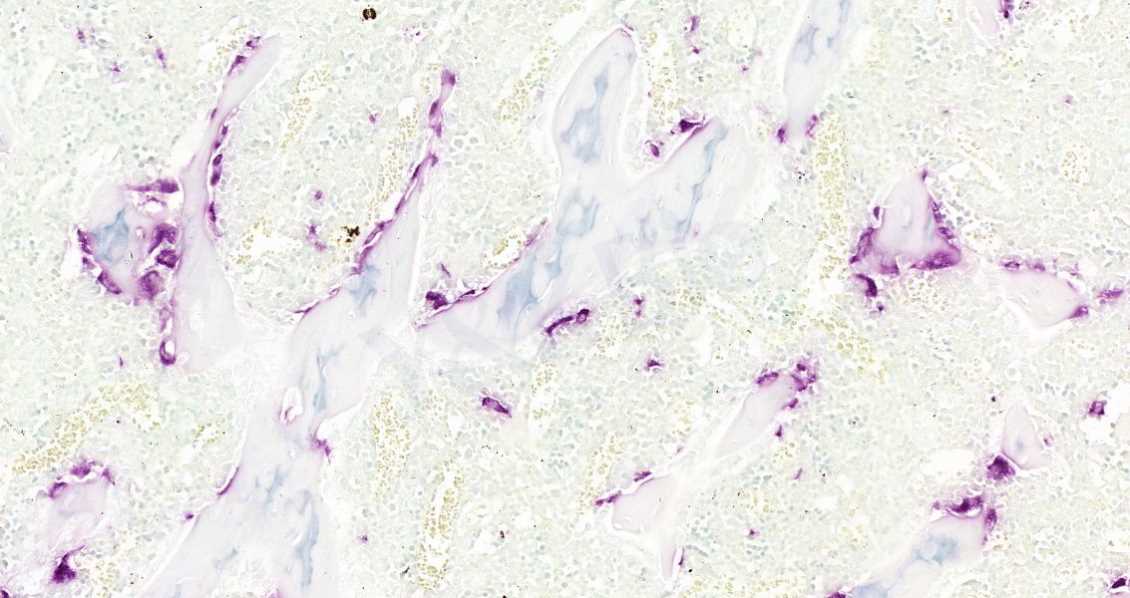

4.Trap染色

Trap染色是用于检测骨组织、骨细胞中特征物质的染色,使破骨细胞呈红色,背景呈绿色或蓝色。抗酒石酸酸性磷酸酶(Trap)为破骨细胞的标志酶,特异地分布于破骨细胞中,为破骨细胞所特有,通常作为鉴别破骨细胞的重要标志物。